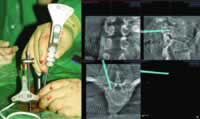

Iso-C 术中即时三维导航在脊柱外科的应用

脊柱外科手术近年得到了很大的发展,但是由于脊椎手术本身特点及脊柱的结构复杂,手术难度和危险性很高。许多手术需要进行复杂的立体操作,这些操作在非可视的情况下进入脊柱的腹地,会进一步增加手术的风险性,如椎弓根固定、寰枢椎关节间固定(Magerl术)及经后路椎体截骨矫形等。因此,更可靠、更安全的智能技术成为大家追求的目标并逐渐变为现实。智能手术首先变为实用技术的是计算机导航系统。随着该技术的逐步发展完善,已显示出精确定位的明显优点,提高了手术的安全性,并且术中X线照射量大大减少。因此越来越多的脊柱外科医师认可并接受了该项技术。

现代脊柱外科计算机导航系统主要使用的是红外线光学导航,该系统分辨率高,可以三维定位,不受手术室内其他设备的干扰 ......